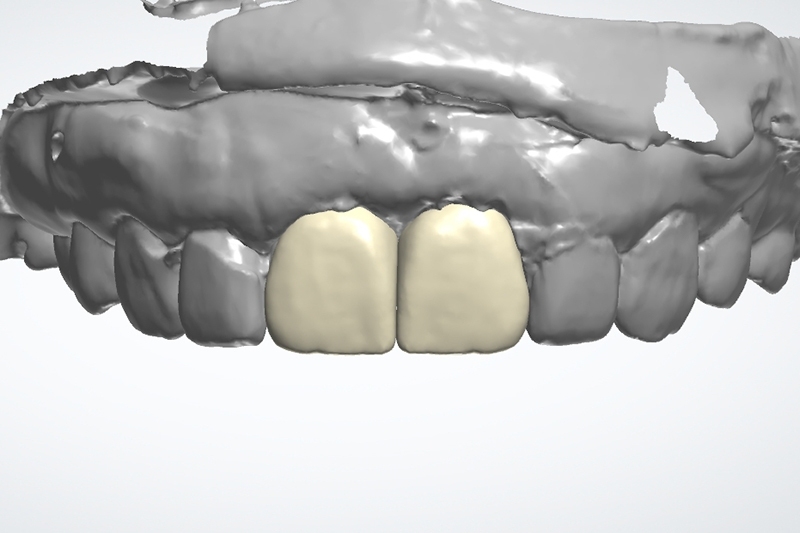

同時數位口內掃描影像取模

利用數位口掃全瓷冠數位設計檔

客製化金屬支台齒